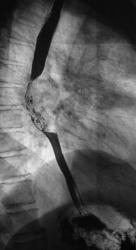

Рентгенограммы и их фрагменты.

Ниже представлены прицельные рентгенограммы пищевода, произведенные в процессе исследования данного пациента, в ортоположении водной взвесью сернокислого бария обычной консистенции.

Ниже рентгенограммы, произведенные на трохоскопе с применением сметанообразной и пастообразной контрастной взвеси.